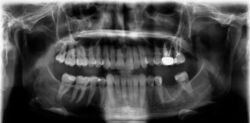

3 wuzelkanalbehandelte Zähne und einen gezogenen Backenzahn später wusste die Patientin, dass diese Beschwerden nicht durch Zähne verursacht wird, wie der damals behandelnde Zahnarzt vermutete.

Es läuft dfas Nachweisverfahren einer CMD unter Einsatz eines adjustierten Aufbissbehelfs.